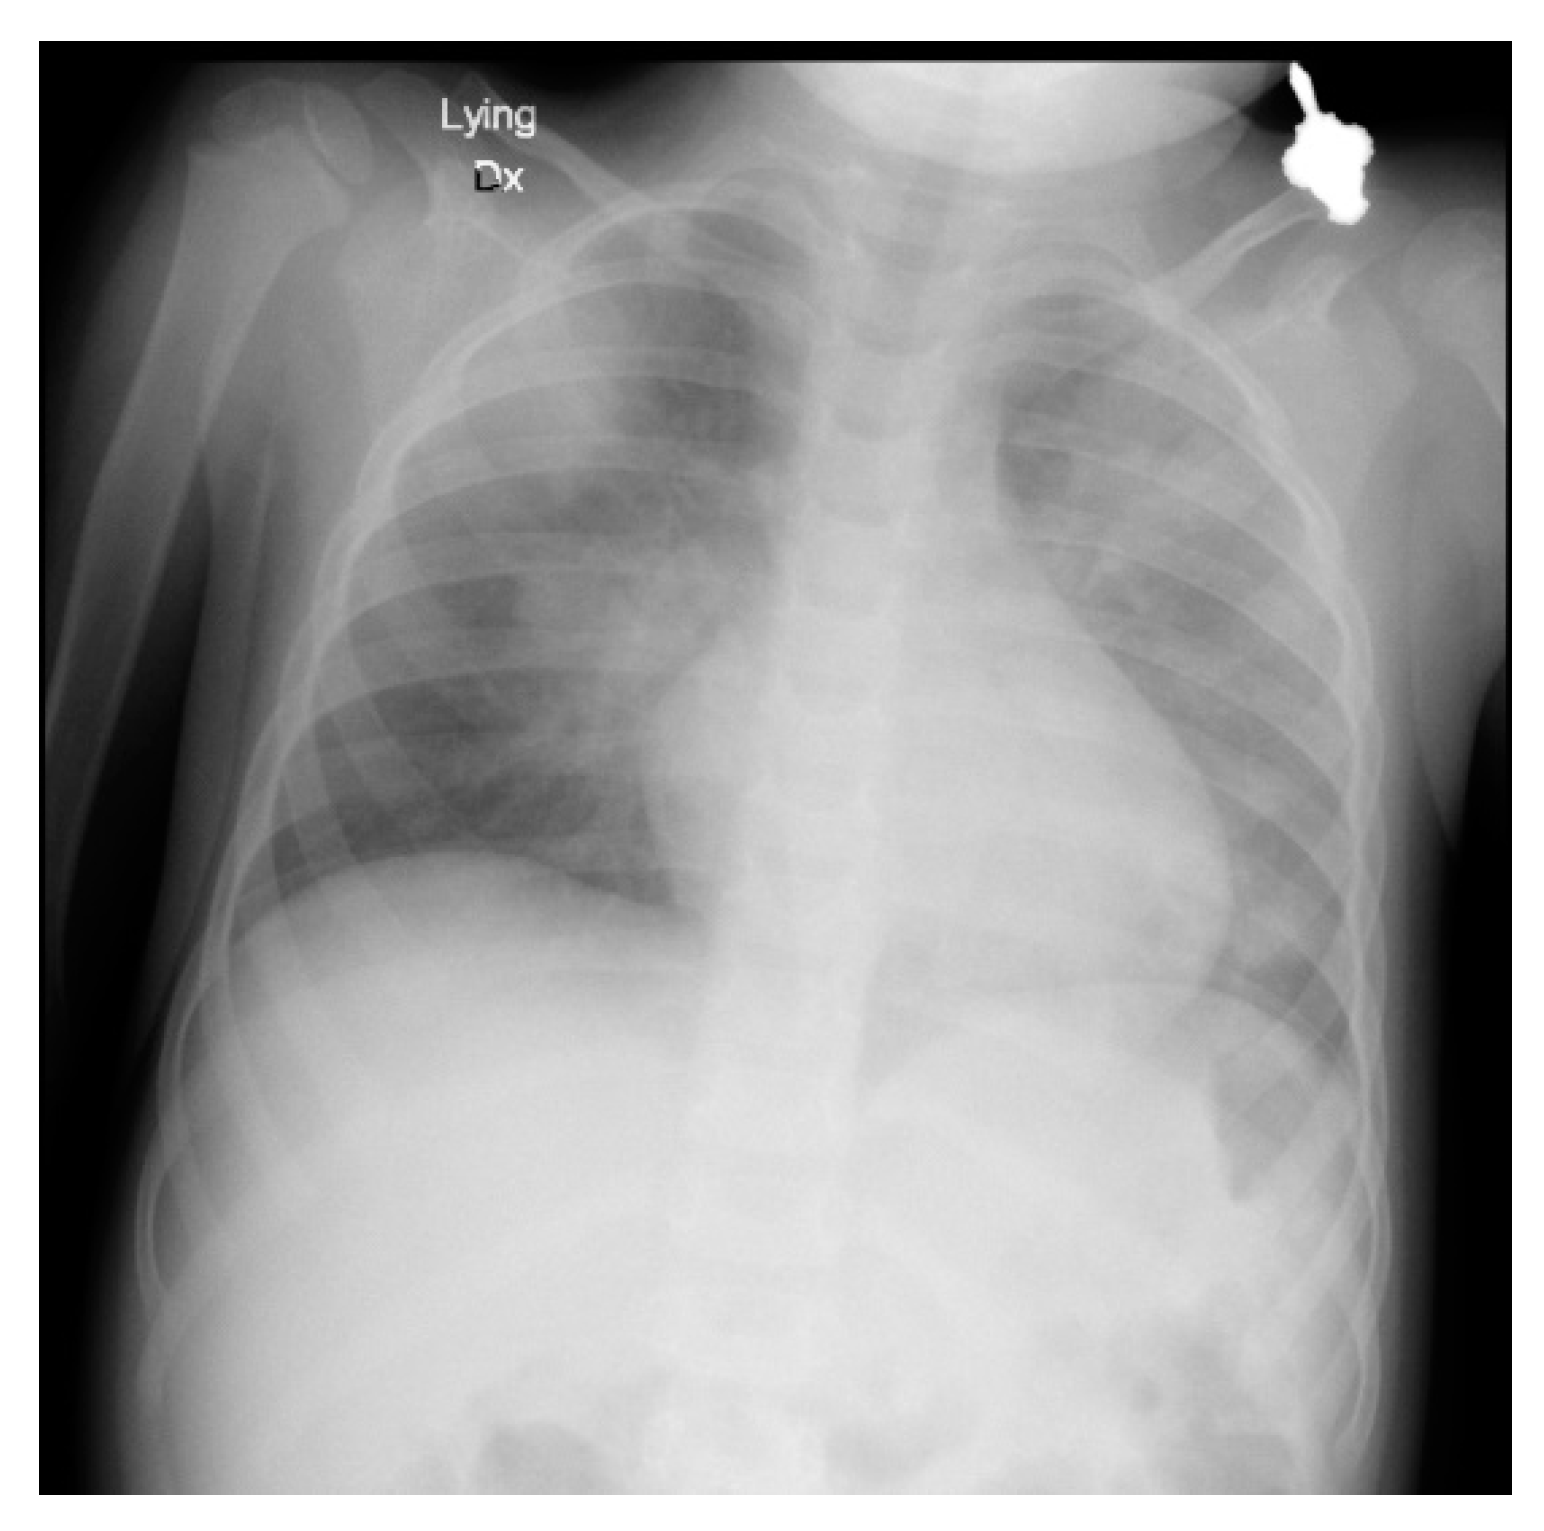

A rapid antigen test performed on admission was SARS-CoV-2 positive. This was confirmed with PCR testing and led to a diagnosis of COVID-19. Over the following four days, the patient’s condition worsened with increasing fatigue, cough, abdominal pain, and tachypnea (reaching 100/min), dropping SpO2 (87–90% on room air). A chest X-ray obtained on day 2 (Figure 1) revealed multiple infiltrates present bilaterally, more pronounced on the left lung than the right, consistent with bilateral pneumonia and a capillary blood gas (CBG) test revealed type I respiratory failure (RF).

Figure 1. Day 2 Chest X-ray demonstrating bilateral pneumonia.